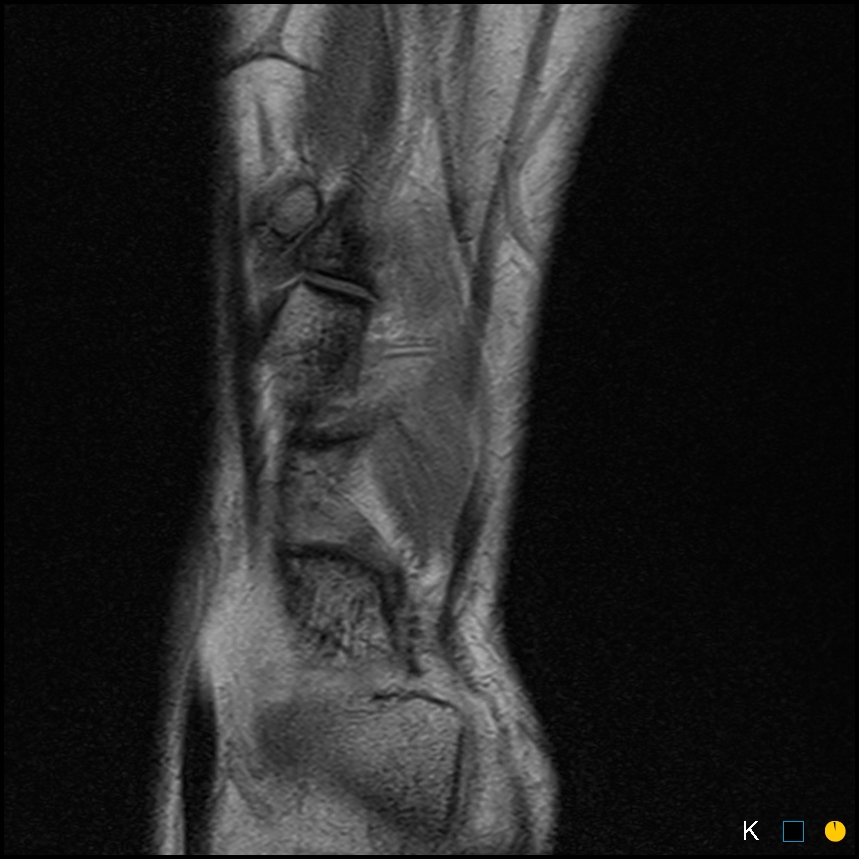

Sprinter. Dorsal midfoot pain

Symptomatic os intermetatarseum

Classification: free standing, articulating and fused

Mostly asymptomatic

Case reports of symptomatic os intermetatarseum in athletes